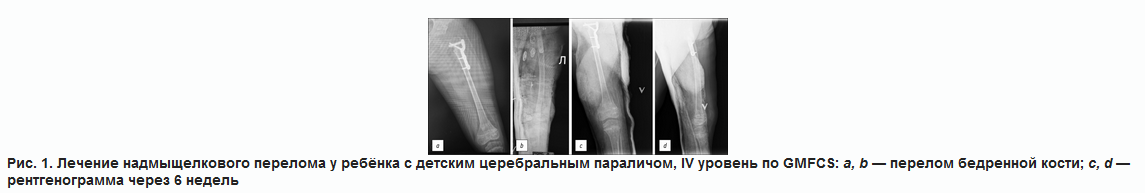

Пример 1. Лечение надмыщелкового перелома бедренной кости гипсовой лонгетой

Ребёнок с ДЦП, IV уровень по GMFCS. Получает терапию по поводу эпилепсии, ремиссия более 2 лет. Индекс массы тела 13,2 кг/м2. Выполнено реконструктивное вмешательство по поводу вывиха бедра. В раннем послеоперационном периоде (через неделю после снятия гипса) на лечебной физкультуре (ЛФК) произошёл надмыщелковый перелом бедренной кости. На рентгенограмме угол смещения незначительный. Выполнена гипсовая иммобилизация. Сращение через 6 недель (рис. 1).